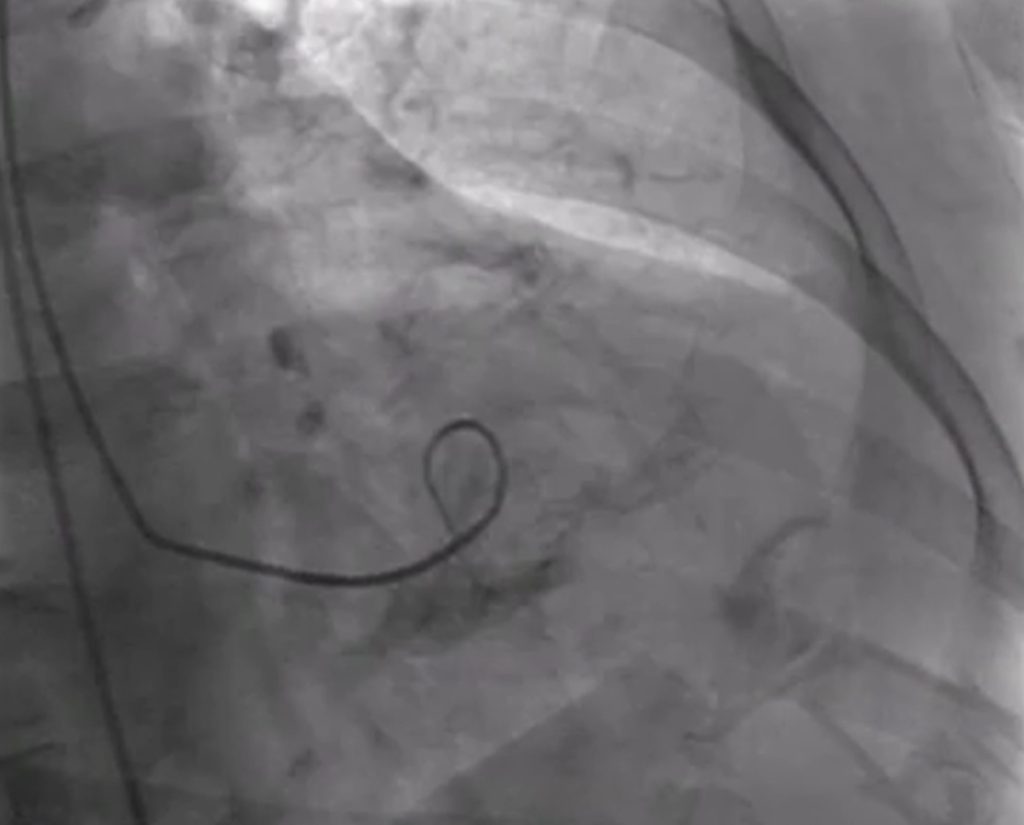

Nos adentraremos en la sala de hemodinámica, y veremos diferentes procedimientos que se realizan para restablecer el flujo sanguíneo y minimizar el daño cardíaco.

La coronariografía permite visualizar las arterias coronarias con contraste, identificando con precisión las obstrucciones responsables del infarto.